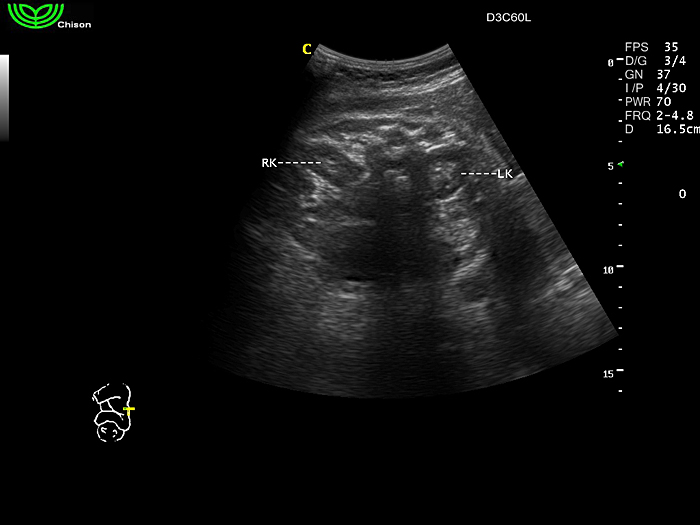

D3C60L 3.5МГц, конвексный.

2.0МГц - 5.8 МГц. Применения: абдомиальное обследование, акушерство, гинекология, обследование районной блокады нерва, осуществление и управление биопсией. |